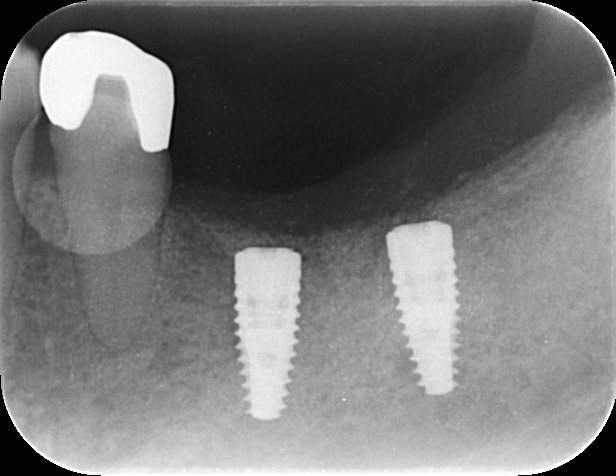

インプラント治療の症例2

レントゲン写真

- Befor

- After

| 年齢 | 50代・男性 |

|---|---|

| 主訴 | 左上7番 左下5番7番 |

| 治療内容 | ・インプラント埋入 ※1:GBR(骨造成)・・・骨再生誘導法。骨の高さや厚みを人工骨や人工膜などを使用し再生する方法 |

| 治療費 | 合計:1,809,500円(税込) ■内訳 ・左上7番 ・左下5番7番 |

| 治療期間 | 左上7番約1年 左下5番7番約10ヵ月 |

| 治療方針 | 左上7番は昔他院で被せものをしており、被せものの中が歯ぐきの中まで虫歯になっていたため抜歯せざるを得ない状態だった。抜歯と同時に骨造成を行い、骨が出来るまで4ヵ月待ってからインプラントを埋入した。 ※2ポンティック・・・歯のない部分を補うダミーの歯。 |

| 担当者所見 | 元々金属の被せものが多く入っていたため、2次カリエス※3が多かった。今回は金属ではなく、ジルコニアを使用し、2次カリエスにならないよう、患者様にはブラッシング指導とメンテナンスの重要性をお伝えした。 ※3二次カリエス・・・詰め物や被せものを入れた歯が虫歯になること。 |